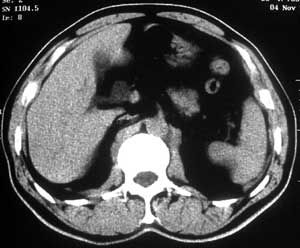

患者,男,57岁,梗阻性黄疸10余天。

这个病例胰头无明显增大,胆总管扩张明显而肝内胆管扩张更不明显,病程较短,

注意到十二指肠乳头明显突出,但尚光滑。分析以下可能性:

1、十二指肠乳头本身的病变,如乳头炎症;

2、急性乳头水肿,胆总管下端结石排石后乳头水肿;

3、壶腹部胆总管下端肿瘤累及十二指肠乳头。

十二指肠乳头粘膜慢性非特异性炎症